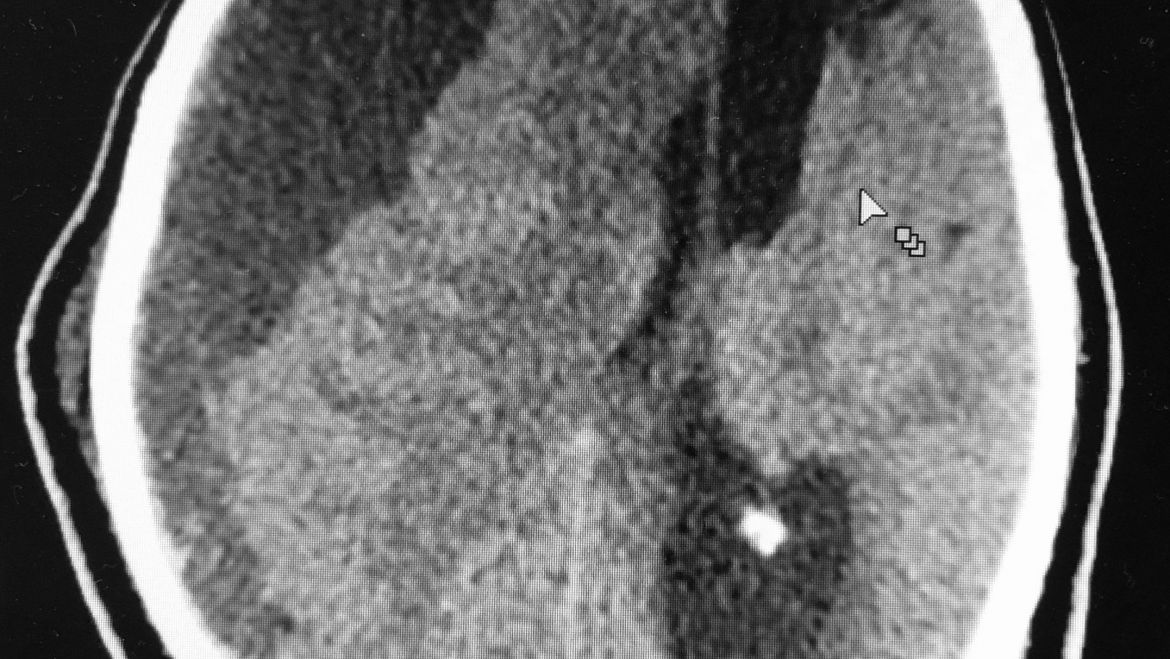

Um hematoma subdural crônico é constituído pela presença de sangramento crônico no espaço subdural, ou seja, abaixo da dura-máter (meninge rígida que envolve o cérebro). Ele se forma inicialmente em decorrência de algum traumatismo craniano, mesmo que mínimo, que cause hemorragia no espaço subdural. Esse sangramento estimula a formação de membranas e deposição de substâncias dentro do hematoma que provocam novos sangramentos, perpetuando o mesmo. Assim, ele pode atingir grandes dimensões como na imagem mostrada.